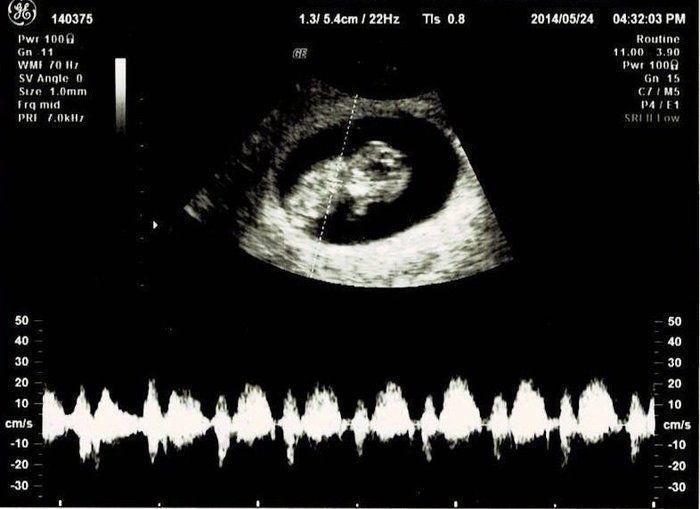

宮本真知さんの妊娠10週目のエコー写真

職場の上司にはこの時点で報告しておきました。「もし、妊娠が継続しなかったら……」ということも考えたのですが、早く伝えたほうが会社にも迷惑がかからないだろうと考えました。このとき、初めて心拍が確認できました。診察後産院の受付に行くと、「赤ちゃんに会える日を楽しみにしています」と書かれたメッセージカードを頂きました。中を開くとエコー写真が。大感激して、今でも大切に取ってあります。